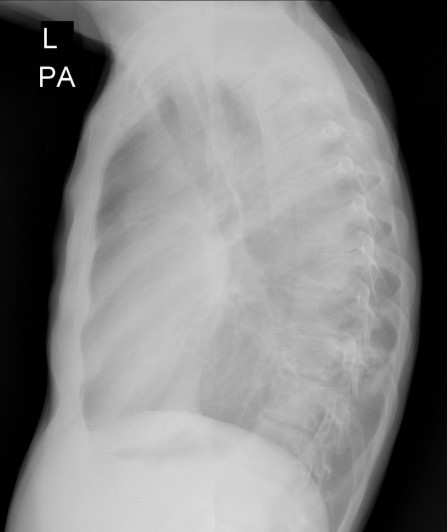

Врачом-рентгенологом Якушевой И.А. было выполнено исследование грудной клетки в 2-х проекциях.

При исследовании в верхушке левого лёгкого было выявлено, субплеврально, полостное образование с толстыми стенками (толщиной до 3,5 мм) с нечёткими и неровными контурами, с прилежанием к костальной плевре на широком основании, размерами 26х22 мм. Вокруг данного образования определялся участок консолидации с прослеживающимися, суженными, деформированными просветами бронхов. Каудальнее образования и участка консолидации определялись хаотично расположенные очаги размером до 7 мм. В S1-2 левого лёгкого субплеврально определялось округлое образование с чёткими, неровными контурами с прилежанием к костальной плевре, размером до 11 мм. В левой плевральной полости жидкостное содержимое с максимальной сепарацией листков плевры до 54 мм, на этом фоне листки плевры были уплотнены, утолщены до 7 мм. На фоне жидкостного содержимого в плевральной полости, в паренхиме левого лёгкого отмечались множественные линейные фиброзные тяжи. В S6, S9 правого лёгкого, перибронховаскулярно, определялись множественные очаги по типу «дерева в почках» (размером до 6 мм), сливающиеся между собой с формированием участка консолидации размером до 27 мм. Кроме того, в правом лёгком определялись множественные мелкие центрилобулярные и субплеварльные очаги уплотнения размером до 4 мм.

С учетом анамнеза и данных МСКТ-исследования было вынесено заключение КТ-картины полостного образования в верхушке левого лёгкого, с наличием участка консолидации, очагов отсева в верхней доле левого лёгкого, субплеврального образования в верхней доле левого лёгкого, левостороннего плеврального выпота, с признаками утолщения листков плевры, фиброзных изменений левого лёгкого, очагов по типу «дерева в почках» с формированием участка консолидации в нижней доле правого лёгкого (данные изменения, вероятно, соответствуют проявлениям вторичного туберкулёза, дифференцированного с периферическим образованием с признаками вторичных изменений. Перелом переднего отрезка 5-го ребра справа.